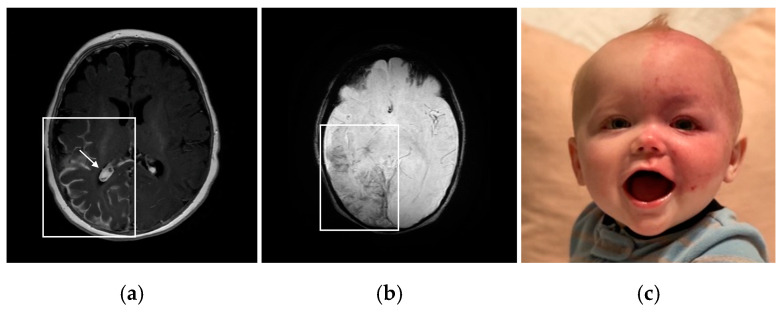

SWS brain involvement is seen in Type 1 (brain and skin, with or without eye involvement) and in Type 3 (isolated brain involvement). Since SWS is a spectrum disorder, it is clinically most useful for patients when clinicians refer to the structures involved (or at risk) rather than using the type classification. The same gene mutation has been shown to be active in both Type 1 and Type 3; the difference is likely in the timing of the mutation during fetal development, impacting structures and cell types involved [ref. 1]. The predominant diagnostic criterion of SWS brain involvement is visualizing the leptomeningeal angiomatosis. Identified on T1-weighted post-contrast magnetic resonance imaging (MRI), leptomeningeal enhancement indicates capillary–vascular malformations of the leptomeninges and impaired superficial venous drainage pathways in the brain [ref. 15]. Other abnormalities that arise over time include cortical and subcortical calcification surrounding blood vessels, as well as the development of enlarged and/or increased deep-draining vessels [ref. 16]. Increased prominence of deep-draining vessels acts to compensate for the elevated venous pressure caused by the capillary–venous malformations of the leptomeninges [ref. 17]. Further, enlargement of the choroid plexus, commonly observed on T1-weighted post-contrast or susceptibility-weighted MRI, can also develop due to venous hypertension and increased flow in the deep venous system resulting from the leptomeningeal vascular malformation [ref. 18]. Observation of peri-vascular brain calcification and atrophy on head computed tomography or susceptibility-weighted imaging on MRI demonstrates the brain injury that develops over time in many patients with SWS (Figure 1a,b) [ref. 19]. Bilateral brain involvement is present in around 15% of patients with SWS, and this subset of patients with SWS usually experience more severe seizures and neurocognitive deficits [ref. 20].

Due to the somatic mosaic nature of SWS during early fetal development, a facial port-wine birthmark (PWB) is a common feature of the disorder. Early laser surgery during infancy is typically recommended to reduce the vascularity of the birthmark and prevent tissue hypertrophy, blebbing, and bleeding, which frequently happens later in childhood or adulthood in these patients [ref. 8]. The PWB mainly presents ipsilateral on the face in relation to the location of brain involvement [ref. 2]. Patients with a PWB are susceptible to other dermatological complications, such as excessive nose or gum bleeds. The GNAQ mutation is considered a driver mutation, making affected tissues particularly vulnerable to other mutations and vascular proliferation [ref. 9]. Presentation of a PWB at birth is one of the early indicators of SWS; however, it is possible for a patient to have brain involvement and not have a PWB. Patients with unilateral PWB presentation have a ~25% risk of increased SWS symptom severity, and those with bilateral presentation have a ~35% risk of symptom severity [ref. 10]. Many patients with SWS have a PWB that also covers the upper and lower eyelids, often indicating impaired ocular vasculature and a high risk of glaucoma (Figure 1c) [ref. 2].